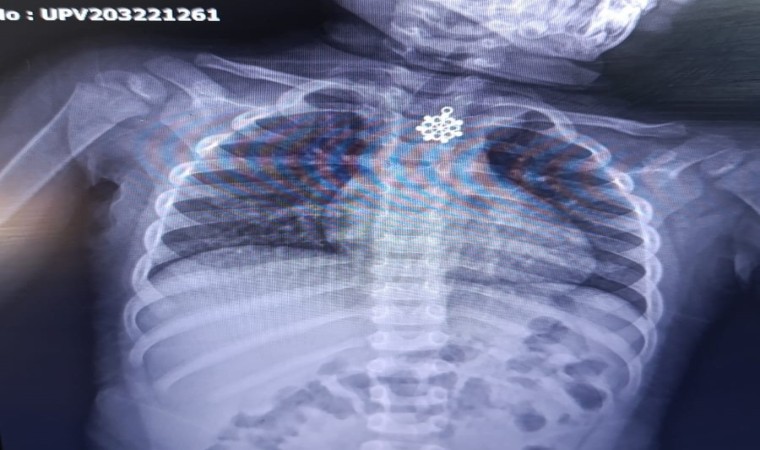

Boğazlarına yabancı cisim kaçan ve idil ile Şırnak Devlet Hastanelerinden Cizre Devlet Hastanesine sevk edilen 3 çocuk Göğüs Cerrahi Uzmanı Op. Dr. Serdar Munis’in bronkoskopi ve özufagoskopi cihazı ve ameliyat ortamında yaptığı başarılı tıbbi müdahale ile sağlıklarına kavuştu. 2,5 yaşındaki Ali Asaf Kutlu, 3 yaşındaki Maşallah Aydın ve 5 yaşındaki Miraç Akhan Op. Dr. Serdar Munis’in bronkoskopi ve özufagoskopi cihazı ile ameliyat ortamında yaptığı başarılı tıbbi müdahale ile sağlığına kavuştu.

Rijit bronkoskopi ve özufagoskopi cihazlarının Şırnak’ta bulunmasının hastalar açısından hayati bir öneme sahip olduğuna vurgu yapan Cizre Dr. Selahattin Cizrelioğlu Devlet Hastanesi Göğüs Cerrahi Uzmanı Op. Dr. Serdar Munis, "Şırnak ili genelinde rijit bronkoskopi ve özufagoskopi cihazları olmadığından dolayı hastayı hayatı riske sokan böylesi durumlarda, hastalar ambulanslar ile bu müdahalenin yapıldığı en yakın merkez olan Diyarbakır’daki sağlık kuruluşlarına sevkleri yapılmaktaydı. Bu cihazların temininden sonra çok kısa bir zaman diliminde 3 hastaya müdahale edilmiş olup 3 hastanın nefes ve yemek borularına kaçan yabancı cisimler çıkartılmıştır. Hastalara yerinde ve erken müdahale edilmeleri, hem hastaların sağlığı açısından, hem de sağlık çalışanlarının iş yükünü hafifletmek açısından yerinde bir sağlık müdahalesi imkanı olmuş ve hastalarımız yapılan tıbbi müdahale ile sağlıklı bir şekilde taburcu edilebilmişlerdir" dedi.